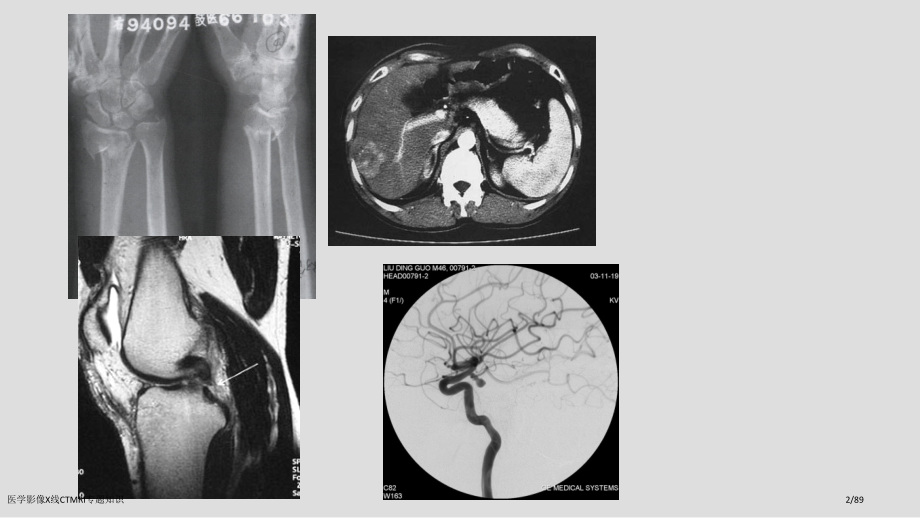

单击此处编辑母版标题样式,单击此处编辑母版文本样式,第二级,第三级,第四级,第五级,2021/10/1,#,医学影像,医学影像系,医学影像X线CTMRI专题知识,1/89,医学影像X线CTMRI专题知识,2/89,第一篇 总论,概述,X线成像,CT,MRI,不一样成像观察、分析及综合应用,PACS与信息放射学,医学影像X线CTMRI专题知识,3/89,威廉康拉德伦琴(Wilhelm Conrad Roentgen),(1845-1923),伦琴是德国吉森大学物理学教授、吉森大学物理研究所所长。他于1895年11月8日下午黄昏在做试验时,发觉了一个可使萤光物质发光射线,当初还弄不清这种射线性质,所以称为,X,线射线。19伦琴教授成为第一个诺贝尔物理学奖得主,医学影像X线CTMRI专题知识,4/89,影像诊疗学,X线,放射诊疗学,超声成像(Ultrasonography:US),核素显像:包含,闪烁成像,发射体层成像(,Emission Computed Tomography,ECT),单光子发射体层成像(SPECT),正电子发射体层成像(PET),CT(Computed Tomography),MRI(Magnetic Resonance Imaging),医学影像X线CTMRI专题知识,5/89,1896年,德国西门子企业制出世界上第一只X 线管。20世纪10代,出现了常规X线机,医学影像X线CTMRI专题知识,6/89,医学影像X线CTMRI专题知识,7/89,1972年,英国工程师亨斯菲尔德 (G.N.Hounsfield)研制第一台CT机。,医学影像X线CTMRI专题知识,8/89,1983年螺旋CT,医学影像X线CTMRI专题知识,9/89,1979年磁共振成像(MRI)设备,医学影像X线CTMRI专题知识,10/89,1954年B超问世,医学影像X线CTMRI专题知识,11/89,1979年SPECTPET,医学影像X线CTMRI专题知识,12/89,影像诊疗学,利用各种成像技术,使人体内部结构和器官成像,借以了解人体解剖与生理功效情况及病理改变,以到达诊疗目标,是特殊诊疗方法。,医学影像X线CTMRI专题知识,13/89,影像诊疗学发展,普通X线影像向数字方式发展无胶片化(Filmless)发展,扫描速度向4层以上或容积CT发展透视、螺旋扫描无限制、软件功效愈加强大(实时三维成像、实时血管成像、实时手术路径等),向开放式发展,扫描时间与相同甚至更加快,磁共振透视功效深入完善,分子影像学,计算机辅助检测,图象存档与传输系统(PACS),医学影像X线CTMRI专题知识,14/89,介入放射学,是以影像诊疗学为基础,在影像设备导向下利用经皮穿刺和导管技术等,对一些疾病进行非手术治疗或以取得组织学、细菌学、生理和生化材料,以明确病变性质一门学科,70年代兴起,属于微创医学范围。,三大治疗体系:内科、外科、介入,医学影像X线CTMRI专题知识,15/89,一、影象监视设备,医学影像X线CTMRI专题知识,16/89,医学影像X线CTMRI专题知识,17/89,医学影像X线CTMRI专题知识,18/89,髂总动脉动脉瘤带膜支架封堵术,医学影像X线CTMRI专题知识,19/89,医学影像学:,影像诊疗学,介入放射学,医学影像X线CTMRI专题知识,20/89,注意事项,1、了解不一样成像技术原理及图象特点,2、掌握图象观察和分析方法,3、了解不一样成像伎俩在不一样疾病诊疗作用与程度,4、必须结合临床资料,综合诊疗,医学影像X线CTMRI专题知识,21/89,医学影像X线CTMRI专题知识,22/89,了解CT检验原理(CT图像特点),肝内胆管结石,digital imaging&CT number,密度分辨率CT远远高于平片,医学影像X线CTMRI专题知识,23/89,正常颅脑T1加权像(T1WI),医学影像X线CTMRI专题知识,24/89,正常颅脑T2加权像(T2WI),医学影像X线CTMRI专题知识,25/89,医学影像X线CTMRI专题知识,26/89,80岁女性 发病6小时内,医学影像X线CTMRI专题知识,27/89,第一章 X线成像,第一节 普通X线成像,一、X线成像基本原理与设备,(一、)X线产生和特征,1、,X线产生,:是真空管内高速行进电子流,轰击钨靶时产生,X线发生装置主要包含:X线管、变压器、,操作台,医学影像X线CTMRI专题知识,28/89,医学影像X线CTMRI专题知识,29/89,医学影像X线CTMRI专题知识,30/89,2、X线特征,波长:0.000650nm,X线诊疗惯用波长:0.0080.031nm,与X线成像相关特征:,穿透性,荧光效应,感光效应,电离效应(生物效应),医学影像X线CTMRI专题知识,31/89,与成像相关特征,穿 透 性,:,能穿透可见光不能穿透各种不一样密度物体,此为X线成像基础(吸收与衰减,穿透与管电压,厚度与密度),荧光效应,:,能激发荧光物质发出可见光,此为X线透视基础,摄影效应,:,能使涂有溴化银胶片感光并形成潜影,以显定影处理产生黑、白图像。此为X线摄影基础,电离效应,:,X线经过任何物质都可产生电离效应,此为X线防护和放射治疗基础,医学影像X线CTMRI专题知识,32/89,X线影像形成原理,X线影像形成原理:,X线特征,被摄物提存在密度和厚度差异。,医学影像X线CTMRI专题知识,33/89,不一样密度成像原理,医学影像X线CTMRI专题知识,34/89,不一样厚度成像原理,医学影像X线CTMRI专题知识,35/89,X线图像是由从黑到白不一样灰度影像所组成,是灰阶图像,医学影像X线CTMRI专题知识,36/89,二、X线图像特点,灰阶图像,反应人体组织结构解剖及病理状态,重合、放大、失真,医学影像X线CTMRI专题知识,37/89,医学影像X线CTMRI专题知识,38/89,密度,物质密度和影像密度:,组织密度组织X线吸收率溴化银还原照片白(高密度),组织密度组织X线吸收率溴化银还原照片黑(低密度),对比:组织密度差异,人体可分为骨骼、软,组织(包含液体)、脂肪和体内气体。天然对比:人体内天然存在密度差异,人工对比:人工方法将造影剂导入体内,增大 密度差异。,医学影像X线CTMRI专题知识,39/89,医学影像X线CTMRI专题知识,40/89,医学影像X线CTMRI专题知识,41/89,三、X线检验技术,(一)、普通检验,荧光透视(fluoroscopy),可转动病人,改变方向观察,可了解器官动态改变,经济简便,马上得到结果,X线摄影(radiography),成像效果好,显示病变清楚,客观统计、便于复查对照和会诊,医学影像X线CTMRI专题知识,42/89,三、X线检验技术,(二)、特殊检验,软线摄影:用于乳腺等软组织摄影,放大摄影:用于显示微细病变,荧光摄影:用于集体体检,记波摄影:用于观察脏器运动,医学影像X线CTMRI专题知识,43/89,三、X线检验技术,(三)、造影检验,1、对比剂,(1).高密度对比剂(阳性对比剂),(2).低密度对比剂(阴性对比剂),2、造影方法,(1).直接引入,(2).间接引入,3、造影前准备及造影反应处理,医学影像X线CTMRI专题知识,44/89,(三)、造影检验,(1)对比剂(contrast media),对比剂条件:,有良好造影效果,无毒无害,能在短时间内排出体外,医学影像X线CTMRI专题知识,45/89,1.阳性(高密度)对比剂:,比重大,原子序数高 惯用钡剂和碘剂等,钡剂(barium),硫酸钡粉末加水和胶配成,以W/V表示,混悬液,:,用于食道及胃肠造影或气钡双重,钡胶浆,:,主要用于支气管造影检验,医学影像X线CTMRI专题知识,46/89,医学影像X线CTMRI专题知识,47/89,医学影像X线CTMRI专题知识,48/89,碘 剂,有机碘制剂,:,用途:,血管,胆道,胆囊,泌尿造影及CT增强,排泄:,经肝或肾,从胆道或泌尿道排出,类型:,离 子 型:,副作用大,过敏反应多,价格低,非离子型:,低渗,低粘度,低毒性,高费用,无机碘制剂,:,用于气管,输尿管,膀胱造影等,如碘化油、碘化钠等,医学影像X线CTMRI专题知识,49/89,医学影像X线CTMRI专题知识,50/89,医学影像X线CTMRI专题知识,51/89,2.阴性(低密度)对比剂:,比重小,原子序数比较小,气 体,种类:,空气、氧气、二氧化碳等,用途:,蛛网膜下腔、关节、腹腔、血管等,优缺点:,空气和氧气吸收慢,反应时间长在血管内易形成气栓,二氧化碳反应小,溶解度大,吸收快,医学影像X线CTMRI专题知识,52/89,(二)造影方式,直接引入:,口服法灌注法穿刺注入法,间接引入:,先引入某一特定组织或器官,再经吸收聚集于造影器官,如淋巴造影,静脉胆道,肾盂造影,口服胆囊造影。,医学影像X线CTMRI专题知识,53/89,(三)检验前准备与造影反应,各种造影检验都应作好对应检验前准备和注意事项,在对比剂中,钡剂应用较安全;气体造影应注意预防气栓发生;碘剂过敏反应较常见,也较严重,医学影像X线CTMRI专题知识,54/89,(四)碘剂造影反应,轻度,:,皮肤潮红,荨麻疹,胸闷,气短,,恶心,呕吐,中度,:,意识丧失,喉头水肿,呼吸困难,重度,:,血压下降,肺水肿,心脏骤停,休克、死亡,医学影像X线CTMRI专题知识,55/89,(五)碘剂造影反应预防,了解病人有没有造影检验禁忌证,如严重心、肾疾病及过敏体质等,过敏试验。30%对比剂1ml静脉注射后观察15分钟,看有没有异常反应,但试验后即使无阳性结果也可发生对比剂反应,作好抢救准备,医学影像X线CTMRI专题知识,56/89,三、X线检验技术,(四)、X线检验方法选择,安全、简便、经济,医学影像X线CTMRI专题知识,57/89,X线诊疗临床应用,仍是影像诊疗中使用最多和最基本方法;,呼吸系统和骨关节系统多首先使用X线检验;,一些部位,如胃肠道仍主要使用X线检验;,神经系统及腹部实质脏器检验主要依靠其它当代影像伎俩。,医学影像X线CTMRI专题知识,58/89,X线检验防护标准,屏蔽,距离,时间,医学影像X线CTMRI专题知识,59/89,X线分析与诊疗,X线诊疗标准和步骤,全方面观察(良好习惯和科学作风),详细分析(X线解剖知识和思维),病灶大小、数目、形态、边缘、内部结构,器官本身功效改变、对临近组织结构影响,推测病了解剖状态(医学基础知识和思维),结合临床资料(临床医学知识和思维),做出X线诊疗(客观公正、实事求是),必定性诊疗、否定性诊疗、可能性诊疗,医学影像X线CTMRI专题知识,60/89,第二节数字X线成像(Digital radiogrophy,DR),产生背景,普通X线成像是模拟成像,摄影技术要求条件严格、曝光宽容度小,影像灰度固定,密度分辨力低,胶片管理,医学影像X线CTMRI专题知识,61/89,DR成像基本原理,将普通X线摄影装置同计算机结合,使X线信息由模拟信息转换为数字信息,而得到数字图象成像技术。,医学影像X线CTMRI专题知识,62/89,DR分类,计算机X线成像:Computed Radiography,CR,数字荧光成像:(digital fluorography,DF),平板探测器数字X线成像:flat panel detectors,医学影像X线CTMRI专题知识,63/89,数字X线成像优点,诊疗资料更多,背影杂波极低,曝光剂量降低,感光宽容度大,可藉电脑处理,影像选择增强,数码摄影系统,资料存放光盘,日后储存传输,可进PACS系统,P,icture,A,rchiving,C,ommnicating,S,ystem,医学影像X线CTMRI专题知识,64/89,CR,以,影像板(IP),代替X线胶片作为介质,IP上影像信息经过读取、图像处理,显示出数字图像,在荧屏上显示人眼可见灰阶图像,保留方式:胶片、磁带、磁盘、光盘,CR,医学影像X线CTMRI专题知识,65/89,医学影像X线CTMRI专题知识,66/89,医学影像X线CTMRI专题知识,67/89,医学影像X线CTMRI专题知识,68/89,医学影像X线CTMRI专题知识,69/89,医学影像X线CTMRI专题知识,70/89,不足,成像速度慢,以分计;,无透视功效;,图像质量仍不够满意.,医学影像X线CTMRI专题知识,71/89,DF,与CR都是将模拟X线信息转换成数字信息,但采集方式不一样,CR用IP,DF用,影像增强电视系统(IITV),,在图象显示、存贮及后处理方面基本相同。,医学影像X线CTMRI专题知识,72/89,DF和CR都是先将X线转换成可见光,再转成电信号,因为有经摄影管或激光扫描转换成可见光再行光电转换过程,信号损失多,图象不如平板清楚,将DF和CR称为间接数字X线成像(indirect digital radiography,IDR),将平板探测器数字X线成像称为直接数字X线成像(direct digital radiography,DDR),医学影像X线CTMRI专题知识,73/89,平板探测器数字X线成像,用平板探测器将X线信息转换成电信号,再行数字化。,X线信息损失少、图象质量好,成像快,是今后发展方向。,缺点:昂贵,不能与原有X线机匹配。,医学影像X线CTMRI专题知识,74/89,DR临床应用,成像速度快、图像质量高,照射剂量低,高级临床应用和后处理功效也正在不停扩展:组织均衡、双能量减影、放大、翻转等,增加了准确诊疗信心,医学影像X线CTMRI专题知识,75/89,组织均衡,利用DR及其宽广曝光动态范围将标准DR图像分解成许多反应不一样密度区域图像,将其加权整合,得到一幅新图像,整个视野内不一样密度组织都能得到良好显示,医学影像X线CTMRI专题知识,76/89,能量减影(定义),利用单次或双次能量曝光法,得到一幅经加权减影技术处理特殊图像,该技术能提供三种解剖学视读影像,常规X线照片影像(原始影像),骨减影影像,软组织减影影像,医学影像X线CTMRI专题知识,77/89,病例1:,呼吸困难1年,加重2个月。,病理:,小细胞癌,医学影像X线CTMRI专题知识,78/89,病例8:,胸痛半个月。,医学影像X线CTMRI专题知识,79/89,医学影像X线CTMRI专题知识,80/89,骨折伴骨痂形成,医学影像X线CTMRI专题知识,81/89,CR、DF、DDR,CR图像质量差,成像时间长,工作效率低,不能做透视;,DF成像时间短,可行透视,多用于血管造影、DSA和胃肠造影;缺点是不能与普通X线设备兼容;,DDR优势显著,价格昂贵。,医学影像X线CTMRI专题知识,82/89,第三节 数字减影血管造影,Digital Subtraction Angiography,DSA是用计算机处理数字影像信息,消除骨骼和软组织影像,使血管显影清楚成像技术。,医学影像X线CTMRI专题知识,83/89,医学影像X线CTMRI专题知识,84/89,DSA-时间减影法,先实施血管造影使检验部位,连续成像,在系列图像中取血管内尚无造影剂和含造影剂最多图像各一帧,将这同一部位两帧图像数字矩阵,用计算机处理,使两个数矩中代表骨及软组织数字抵销,而代表血管数字保留,再经数/模转换器变为只有血管造影图像,这两帧图像叫做,减影对,,因是在不一样时间摄取,故称,时间减影法,此法易受运动影响而产生,配准不良,,血管含糊,医学影像X线CTMRI专题知识,85/89,医学影像X线CTMRI专题知识,86/89,医学影像X线CTMRI专题知识,87/89,DSA临床应用,血管及其病变显示更清楚,选择性或超选择性插管,可显示直径在200m以下血管及小病变,能够观察血流动态图像,仅用较低浓度对比剂,且用量少,医学影像X线CTMRI专题知识,88/89,DSA临床应用,尤其适合用于心脏大血管检验,了解心内解剖结构异常,观察大血管病变:主动脉夹层、主动脉瘤,主动脉缩窄、主动脉发育异常等,显示冠状动脉、头部及颈部动脉病变,医学影像X线CTMRI专题知识,89/89,